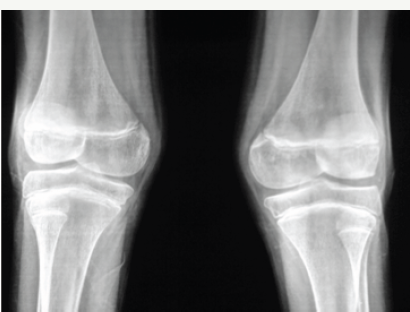

Bowing deformities and knock knees are common in the lower extremities (Figure 3a-3c).

Figure 3 a & b: 6F Rickets, a- Clinical knock knee, b- radiograph knees.

Figure 3 c: Rickets with bowed legs